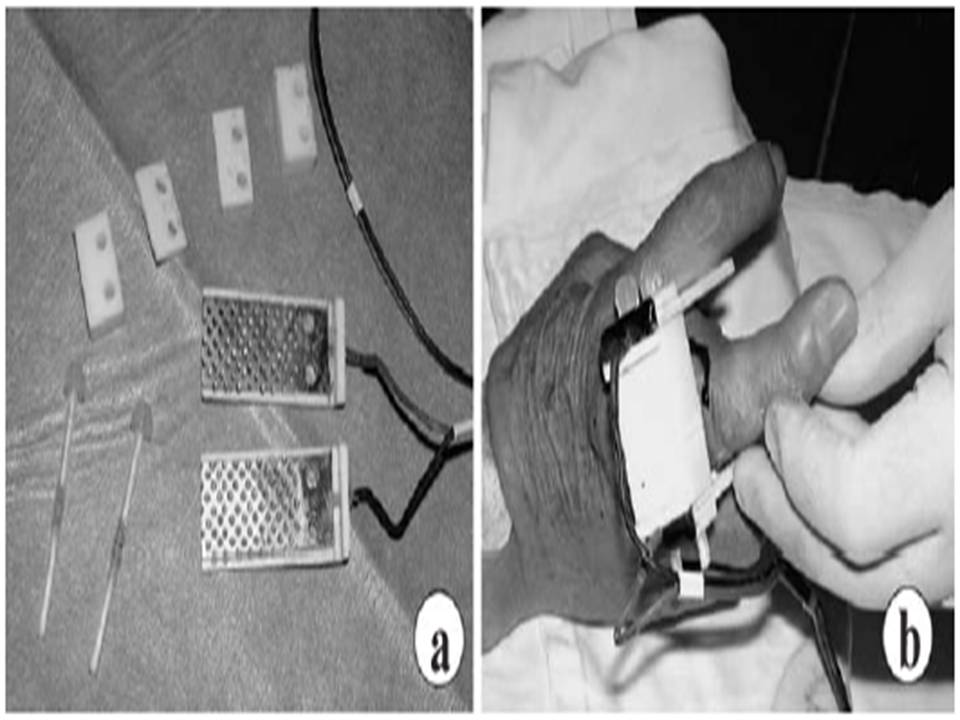

Electrode and electroporation. a. Stainless steel 3cm x 5cm electrodes. b. Electroporation with two parallel electrodes placed on opposite sides of the tumor

Resistance Measurement: 245±101Ω Voltage: 150V (Electric field strength: 50/cm) Current: 1.1±0.5A Pulses:

4 pulses of 250ms (On: 50ms, Off: 200ms) Or 6 pulses of 167ms (On: 50ms, Off: 117ms) |